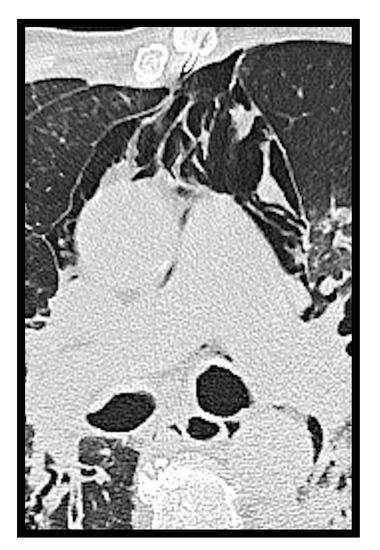

Figure 4. Pericardial effusion on CT, sagittal (A) and axial (B) images, in two patients admitted to intensive care unit. In image B, bilateral pleural effusion is also noted.

Pericardial effusion can be defined as the presence of more than 50 mL of liquid between the pericardial sheets. As already mentioned for the pleural effusion it is not characteristic of the COVID-19 thoracic involvement. In fact, it was observed by Li et al. [8] in 4.8% of cases. However, in this study, it is also described as a manifestation associated with the most compromised patients (Figure 4).

Ali Sabri et al. [13] found a 7.9% frequency of pericardial effusion. Furthermore, from their analysis, it emerged that pericardial effusion could be considered an important factor for admission to intensive care unit (ICU), as it could be an indicator of myocarditis or cardiomyopathy caused by COVID-19, but they did not confirm this hypothesis with echocardiography.

Grassi et al. [9] describe pericardial effusion in 16.7% of patients, proposing a relation with heart damage; Shi et al. [14] associated it with a higher risk of in-hospital mortality.